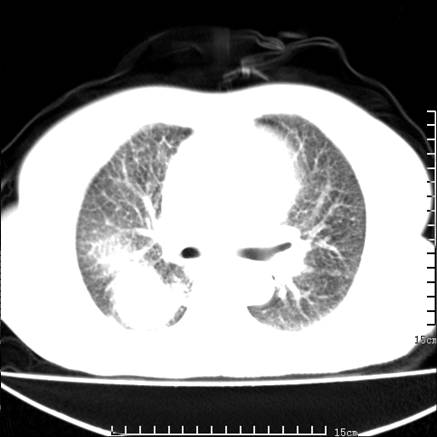

女,王某,58岁,咳嗽三个月余,基层医院二个月前诊为肺结核,用抗结核药二个月无明显疗效。

心包积液致肺瘀血.右侧周围型肺癌伴肺内转移,中间裂积液,叶间胸膜肥厚.右上肺大泡,右侧胸膜肥厚.

双肺继发型tb,心功能不全并肺淤血、心包、双侧叶间裂积液,肺大泡,右下胸膜肥厚钙化。